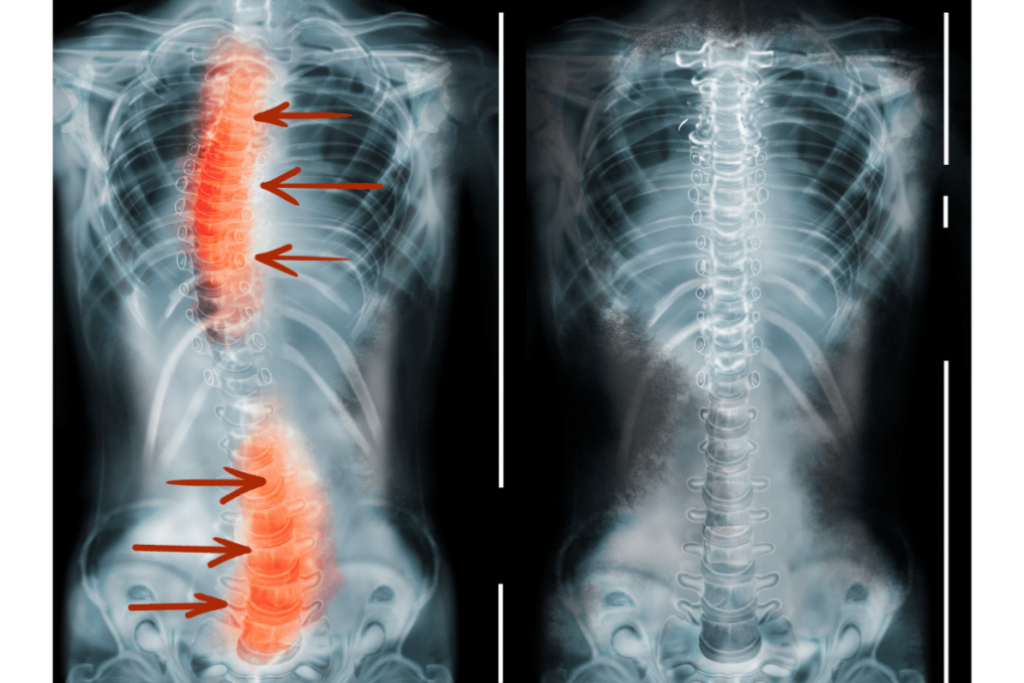

Skolioza je stanje, za katero je značilna nefiziološka ukrivljenost hrbtenice. Človeška hrbtenica je blago ukrivljena v obliki dvojnega S (če jo pogledamo s strani), ob pogledu od spredaj ali od zadaj pa so vretenca poravnana v ravno linijo. Pri osebah s skoliozo pa je hrbtenica ukrivljena vstran, tako da ob pogledu od spredaj ali od zadaj spominja na obliko črke “S” ali “C”. Običajno se razvije v otroštvu ali adolescenci, vendar jo lahko zasledimo tudi pri odraslih, predvsem zaradi degenerativnih sprememb v hrbtenici.

- Rentgensko slikanje – določi kot ukrivljenosti (Cobbov kot), ki je ključnega pomena pri oceni resnosti skolioze. Stopnja ukrivljenosti se meri v stopinjah, pri čemer Cobbov kot 10 stopinj ali več kaže na skoliozo.